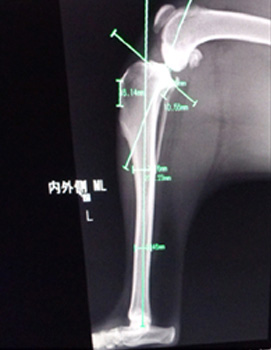

▲術前に手術の角度を決める計測